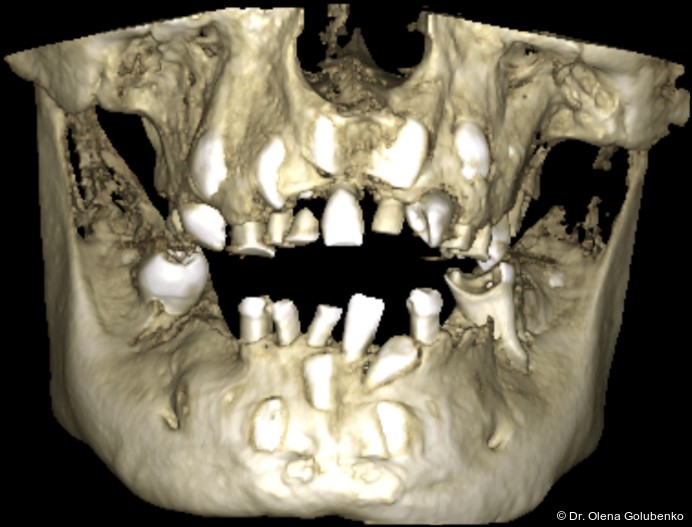

Die dreidimensionale Bildgebung zeigt meist eine hohe Anzahl nicht durchgebrochener permanenter und überzähliger Zähne, die in unterschiedlicher Lage im Kiefer verbleiben (Abb. 3+4).

Die Diagnostik der cleidokranialen Dysplasie basiert auf einer sorgfältigen klinischen Untersuchung, der Analyse von Panoramaaufnahmen sowie insbesondere auf der digitalen Volumentomografie (DVT). Ziel ist es, die Anzahl, Lage, den Entwicklungsstand sowie mög­liche Interferenzen der retinierten und überzähligen Zähne präzise zu erfassen und in ei­nen funktionellen sowie skelettalen Kontext einzuordnen (Abb. 5–8).

• ausgeprägte dentale Anomalien (Abb. 2)